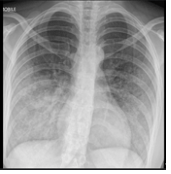

This blunt chest injury often presents with hypoxia out of proportion to chest X-ray findings and is managed primarily with supportive care and oxygenation.

What are pulmonary contusions?

This is the immediate prehospital and ED intervention for an open (‘sucking’) chest wound to prevent tension physiology?

What is a three-sided occlusive dressing?